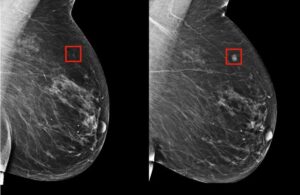

The study, published in the Journal of the American Medical Association Network, analyzed the mammograms of 116,495 women who participated in Norway’s breast cancer detection program between 2004 and 2018. Of these women, 1,607 eventually developed breast cancer. Using a commercially available AI algorithm, the researchers were able to identify women with an elevated risk of developing breast cancer four to six years before diagnosis.

“We noted that the breast which developed cancer had an AI score about twice as high as the other breast,” she said.

The AI’s ability to predict not only the likelihood of cancer but also which breast was at risk spotlights its potential to personalize detection programs.